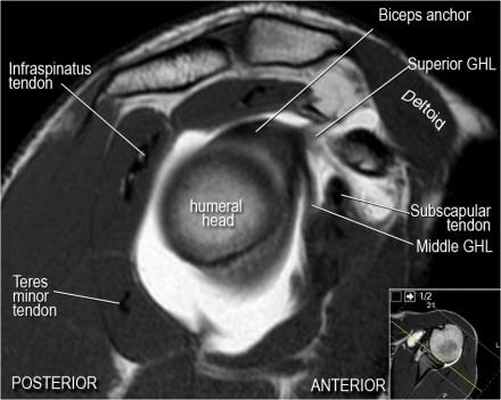

Нормальная анатомия плечевого сустава в аксиальных изображениях и контрольный список.

- обратите внимание что ход сухожилия длинной головки двуглавой мышцы в области прикрепления направлен на 12 часов. Область прикрепления может быть различной ширины.

- обратите внимание на верхние отделы суставной губы и прикрепление верхней плече-лопаточной связки. На данном уровне ищется SLAP-повреждение (Superior Labrum Anterior to Posterior) и варианты строения в виде отверстия под сутавной губой (sublabral foramen - подгубное отверстие). На этом же уровне по задне-боковой поверхности головки плечевой кости визуализируются повреждение Хилл-Сакса.

- волокна сухожилия подлопаточной мышцы, создавая бицепитальную борозду, удерживают сухожилие длинной головки двуглавой мышцы. Изучите хрящи.

- уровень средней плече-лопаточной связки и передних отделов суставной губы. Поищите комплекс Буффорда. Изучите хрящи.